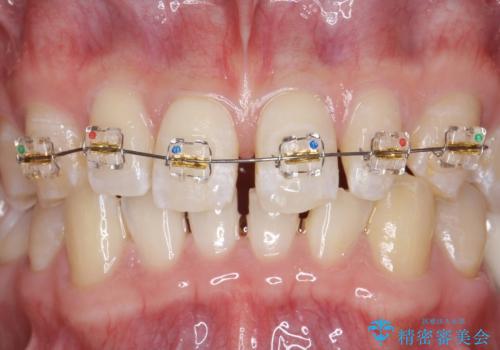

- 上顎前歯のすきっ歯が気になるといらっしゃった方の症例です。

上顎前歯のみの治療を希望されたので、部分矯正を行いました。

左上2の矮小歯はオールセラミッククラウンによる補綴を行いました。